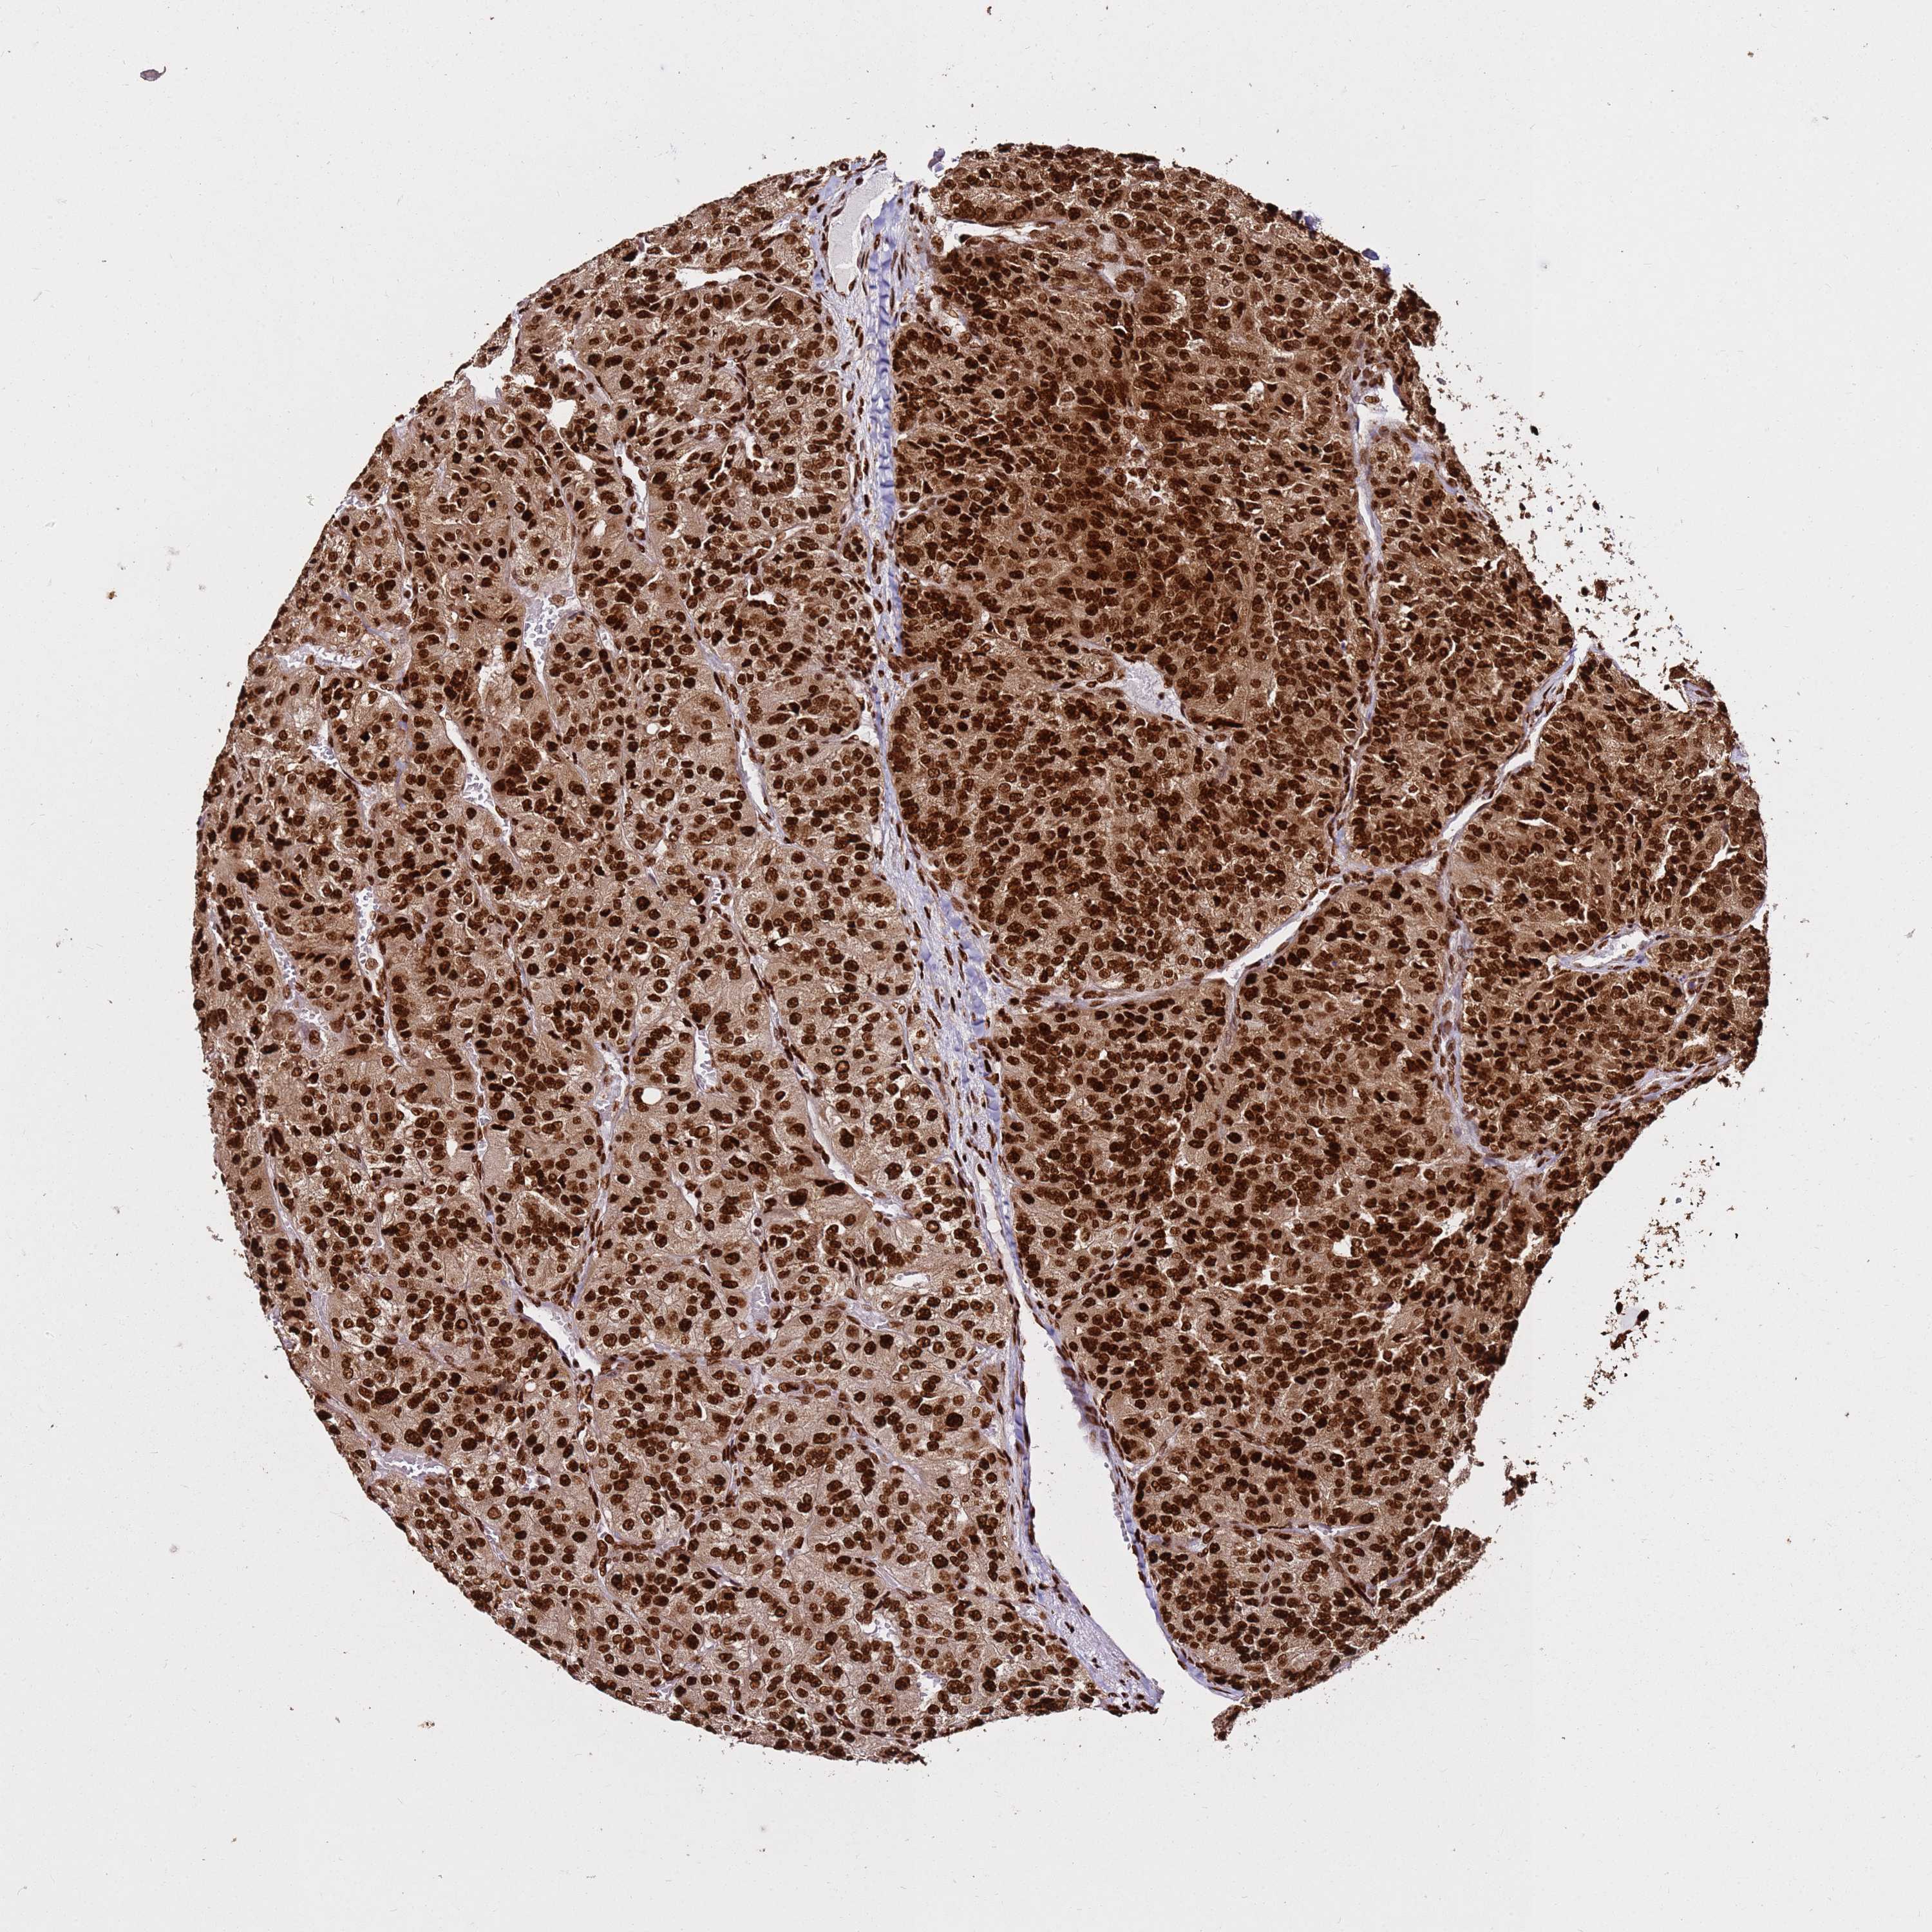

CANCER RENAL CANCER Show tissue menu

KICH TCGA KIRC TCGA KIRC VALIDATION KIRP TCGA PROTEIN RCC CPTAC PROTEIN EXPRESSION

HNRNPAB is potential prognostic, high expression is unfavorable in Kidney Chromophobe (TCGA)

Average pTPM 67.8

Number of samples 64